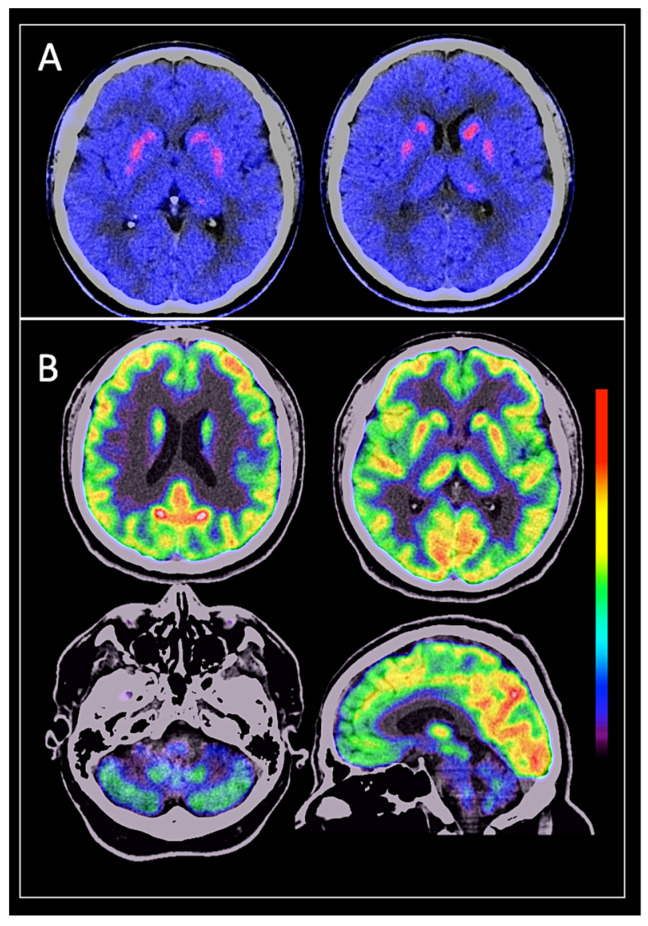

2.2. Imaging Protocol

PET/CT brain imaging acquisitions were performed in a hybrid Siemens Biograph 64 mCT (Siemens Medical Solutions). Dual-tracer FDOPA and FDG were intravenously injected at fixed activities of 185–370 MBq (5–10 mCi) for both radiopharmaceuticals, blood glycemia of ≤150 mg/dl, with at least 4 h of fasting. For the FDOPA scan, 150 mg of carbidopa was administered orally 60 min prior to the radiotracer administration. Dynamic and sequential images were acquired over 90 min. FDG preparation consisted of minimal stimuli, faint lightning, 30–45 min for biodistribution, and wide-open eyes.

The computed tomography (CT) component was performed for attenuation correction and anatomic location, monophasic, 80–100 kV, and 350–380 mA. Transverse PET sections were reconstructed through attenuation correction, based on CT, using an iterative algorithm (ordered subset expectation maximization [OSEM] + time of flight [TOF] + point spread function [PSF]) and a full width at half maximum of 5 mm and 5 iterations.

2.3. Imaging Analysis

FDOPA–FDG dual PET/CT images were evaluated by two nuclear medicine physicians with extensive experience in nuclear neurosciences. They reached a consensus to establish the diagnosis based on imaging patterns, conducting a simultaneous and qualitative visual analysis. This approach was adopted to maximize diagnostic accuracy by integrating the complementary information provided by both radiotracers, thereby overcoming the limitations inherent to each radiotracer when used alone. It is important to note that the nuclear medicine physicians were blinded to the clinical diagnosis to avoid bias, although they were aware that the images came from patients with movement disorders.

For each of the neurodegenerative Parkinsonisms, FDOPA and FDG imaging findings were meticulously analyzed, relying on well-established patterns in the scientific literature.

FDOPA PET: Uptake patterns were assessed based on symmetry and asymmetry in the striatal regions, particularly in the putamen and caudate nuclei. The putamen was subdivided into anterior and posterior regions to evaluate presynaptic dopaminergic dysfunction more precisely, as described in the literature for PD and other atypical Parkinsonisms [ref. 18]. Decreased tracer uptake in the striatal nuclei suggests an alteration in the presynaptic dopaminergic pathway, indicative of a neurodegenerative Parkinsonism. Conversely, normal uptake makes a diagnosis of neurodegenerative Parkinsonism less likely [ref. 19,ref. 20].

FDG PET: Cerebral metabolism was assessed using the same structural configuration of the striatum as in FDOPA PET and included an examination of specific cortical regions. These regions were divided into hemispheres, lobes, and specific surfaces: dorsolateral frontal cortex, medial frontal cortex, dorsolateral temporal cortex, mesial temporal structures, dorsolateral parietal cortex, dorsolateral occipital cortex, anterior and posterior cingulate, precuneus, cuneus, and cerebellar hemispheres. These metabolic patterns are crucial for differentiating between various neurodegenerative Parkinsonisms, as documented in the literature [ref. 21,ref. 22].

Although the nuclear medicine physicians used statistical mapping tools as additional support for analyzing the findings, final diagnosis was primarily based on their clinical expertise and qualitative visual analysis of the images.